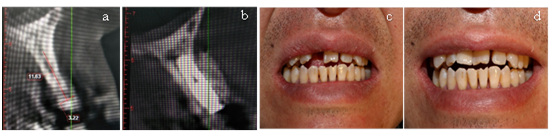

General population: A 56-year-old male patient settled in the plateau area complained pain of his mandibular first molar (Health status: none smoking, fasting blood glucose: 7.8mmol/L).The two mandibular first molars were removed due to vertical root fracture and residual root (Figure 2a). Four months later, the alveolar fossa of 36-tooth was well healed. However, the 46-tooth’s alveolar fossa was healed poorly (Figure 2b).

Surgical plan: The site of left mandibular first molar was implanted with Megagen implant (4.5*10mm). Moreover, the site of right mandibular first molar was placed bone scraps and bone substitutes (Bio-Oss®) and been covered with a resorbable collagen membrane (Bio-Gide®) above. Double-layer membrane technique was applied. Panoramic radiograph showed expected result after operation (Figure 2c). After six months, the result showed that the alveolar fossa of right mandibular first molar had a good osteogenic effect (Figure 2d). The left mandibular first molar’s abutment was repaired with an all-ceramic crown and the site of right mandibular first molar was implanted with Megagen implant (4.5*08mm) (Figure 2e). After three months, the right mandibular first molar’s abutment was repaired with an all-ceramic crown. The patient was reviewed every three months in the first year, and every six months thereafter (Figure 2f).

Figure 2(a) Panoramic radiograph before extraction. (b) Four months later after extraction. (c) Panoramic radiograph after GBR. (d) Six months later after GBR. (e) Panoramic radiograph showed a considerable osteogenic effect around dental implant. (f) Stableosteogenic effect after two years.